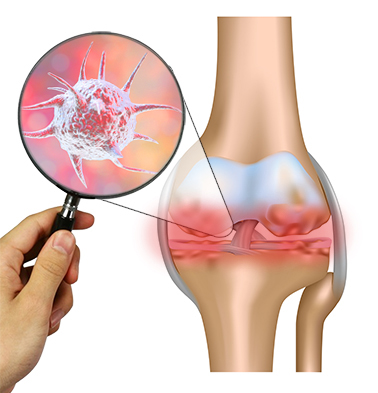

Медицинские состояния: Септический артрит коленного сустава